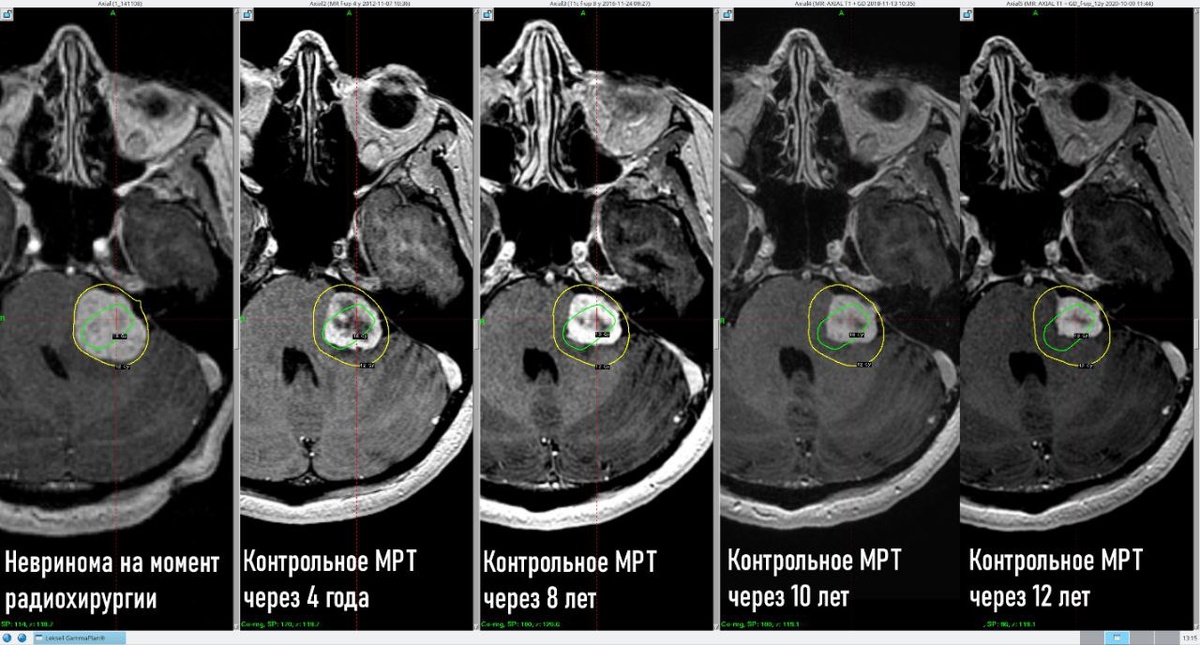

Центр «Гамма-нож» Москва является первым в России центром, который продолжает наблюдать за отдаленными 10 лет и более результатами радиохирургического лечения своих пациентов, что представляет большой интерес для отечественной медицины. Женщина, 49 лет При обследовании по поводу снижения слуха на левое ухо по данным МРТ головного мозга выявлена невринома в проекции левого мостомозжечкового угла с перифокальным отеком, распространяющимся на область левой гемисферы мозжечка. В ноябре 2011 года проведена стереотаксическая радиохирургия. Через 12 лет на контрольном МРТ головного мозга отмечается регресс размеров опухоли до 2.00 см3 (на момент лечения объем составлял 8.5 см3) и её стабилизация в объеме. Состояние пациента удовлетворительное. Жалоб нет.

Через 12 лет на контрольном МРТ головного мозга отмечается регресс размеров опухоли до 2.00 см3 (на момент лечения объем составлял 8.5 см3) и её стабилизация в объеме.